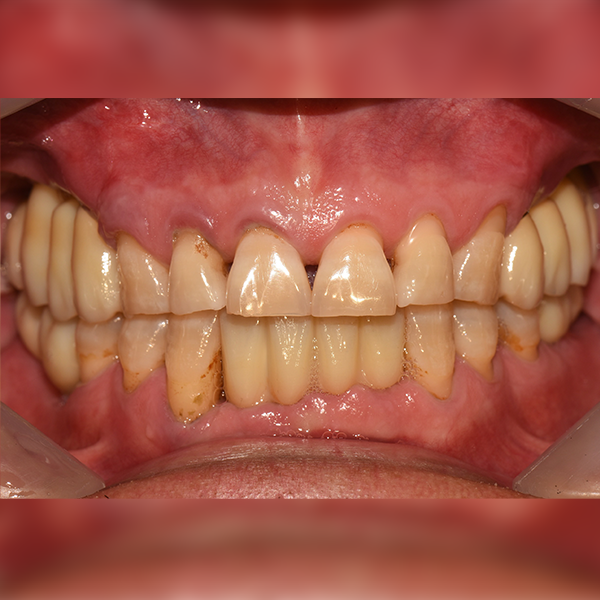

3. Тохиолдол.223 50-аад насны И*ган 2019-01-11 / 2019-07-24

Тохиолдол.223 50-аад насны И*ган 2019-01-11 / 2019-07-24

Before Before

After After